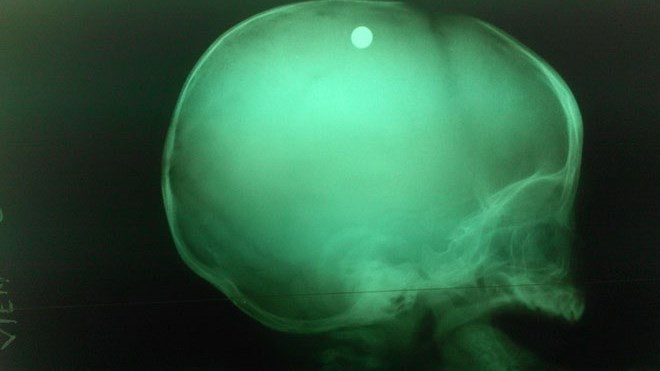

Viên đạn trong đầu bé trai 6 tuổi qua chụp X-quang- ảnh BV nhi đồng 2.

TP - Hôm 6/5, ê kíp bác sĩ Khoa Ngoại thần kinh, Bệnh viện Nhi đồng 2 TPHCM đã phẫu thuật khẩn cấp cứu sống bé trai 6 tháng tuổi ở Bình Phước bị bắn vào đầu.

Bác sĩ Nguyễn Xuân Vinh- Phó Khoa Ngoại thần kinh, Bệnh viện Nhi đồng 2, cho biết bé trai được chuyển đến cấp cứu từ Bệnh viện Đa khoa tỉnh Bình Phước trong tình trạng có một vết thương ở sọ não, lơ mơ, co gồng và đồng tử co nhỏ.

Theo thông tin từ người nhà bệnh nhi, trong lúc bé trai đang chơi với chị gái 6 tuổi thì chị gái cầm khẩu súng tự chế của bố để trong nhà chơi, vô tình súng cướp cò khiến viên đạn bắn thẳng vào đỉnh đầu bé trai.